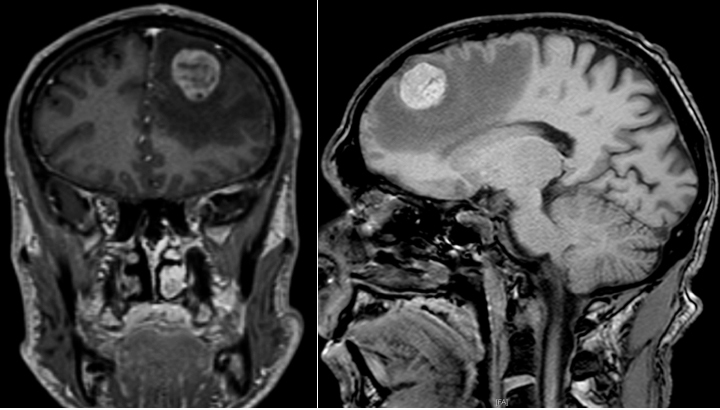

L’association d’une hyper-réflexivité ostéo-tendineuse de l’hémicorps droit avec signes de Hoffmann et de Babinski droits signifie qu’il existe une atteinte de la voie pyramidale droite. Comme le syndrome pyramidal est associé à des troubles de la parole, il faut d’emblée évoquer une origine encéphalique et non pas médullaire. Puisque le syndrome pyramidal est hémicorporel droit, on recherchera une atteinte encéphalique controlatérale, de l’hémisphère gauche, qui explique bien l’association à des troubles de la parole.